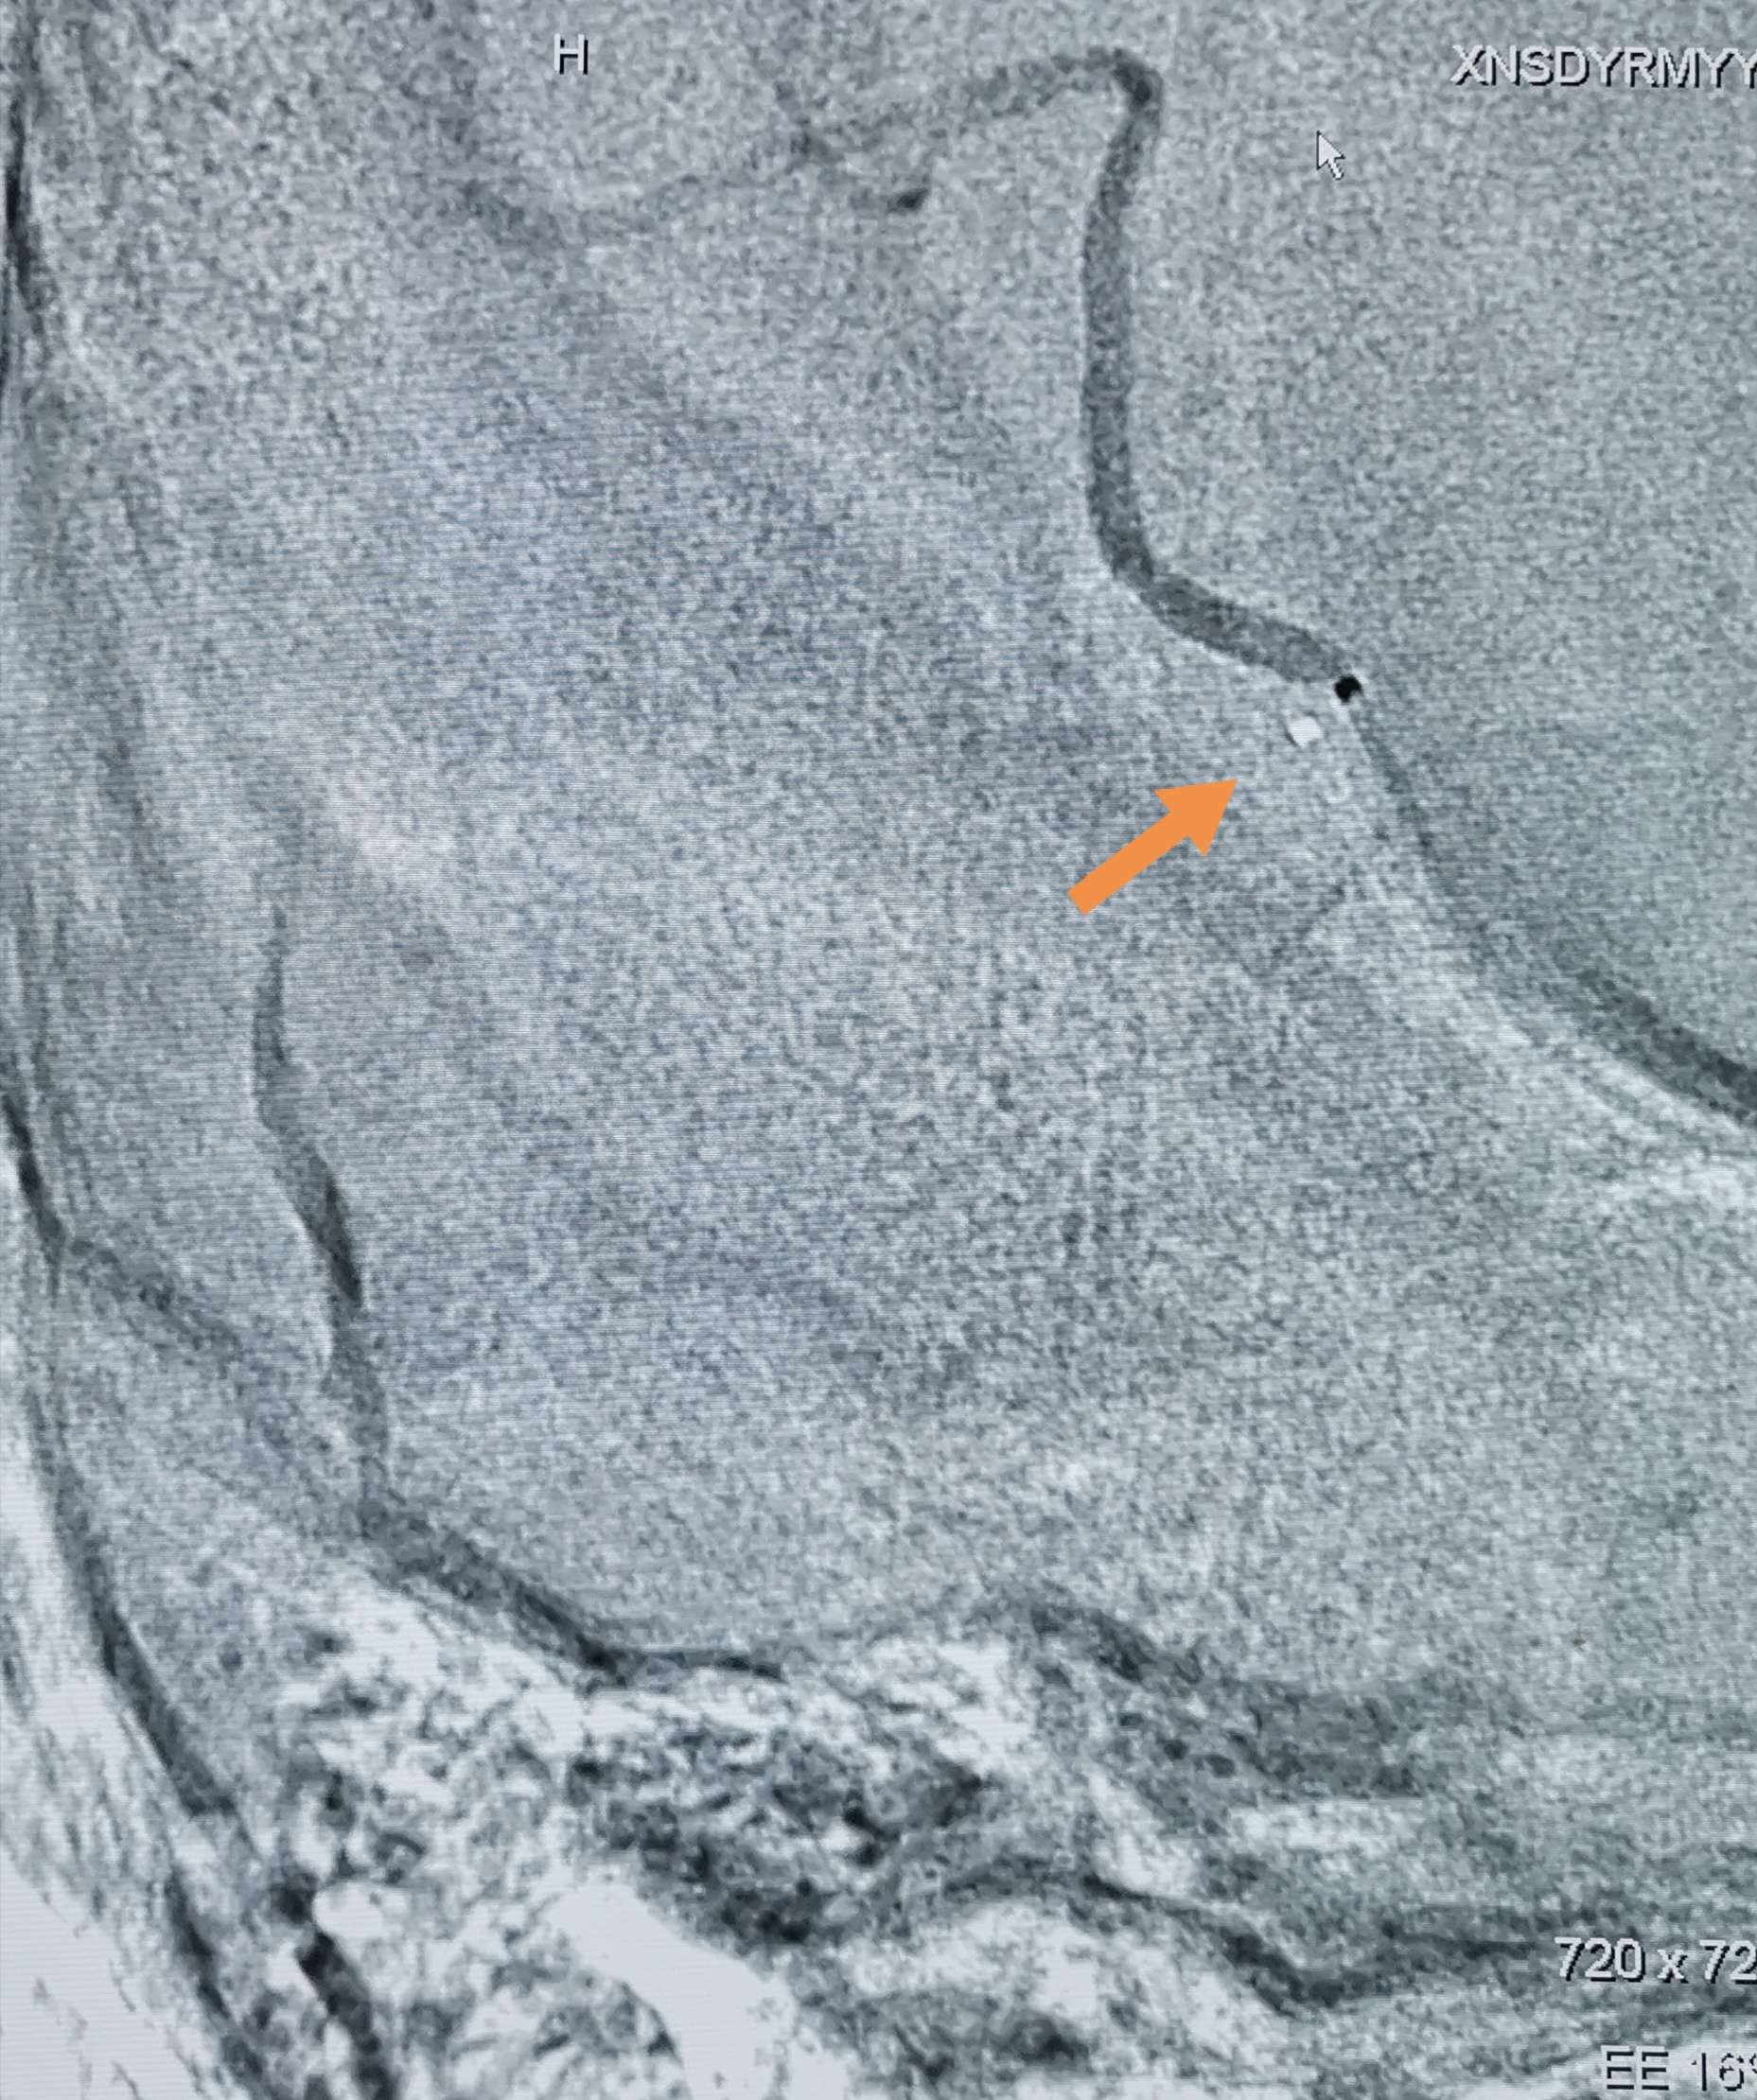

微导管在微导丝引导下通过血栓段